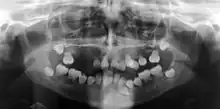

| Preoperative panoramic radiographs showing features of dentin dysplasia type I | |

In other words, affected primary teeth usually have abnormal -shaped or shorter than normal roots. “Crescent/half-moon shaped” pulp chamber remnant in permanent teeth can be seen on x-rays. The roots may appear to be darker or radiolucent/pointy and short with apical constriction. Dentine is laid down abnormally and causes excessive growth within the pulp chamber. This will reduce the pulp space and eventually cause incomplete and total pulp chamber obliteration in permanent teeth.[12][13] Sometimes periapical pathology or cysts can be seen around the root apex.[11] Most cases of DD associated with peri-apical radiolucency/ pathology have been diagnosed as radicular cysts, but some of them have been as diagnosed peri-apical grauloma instead.[14]